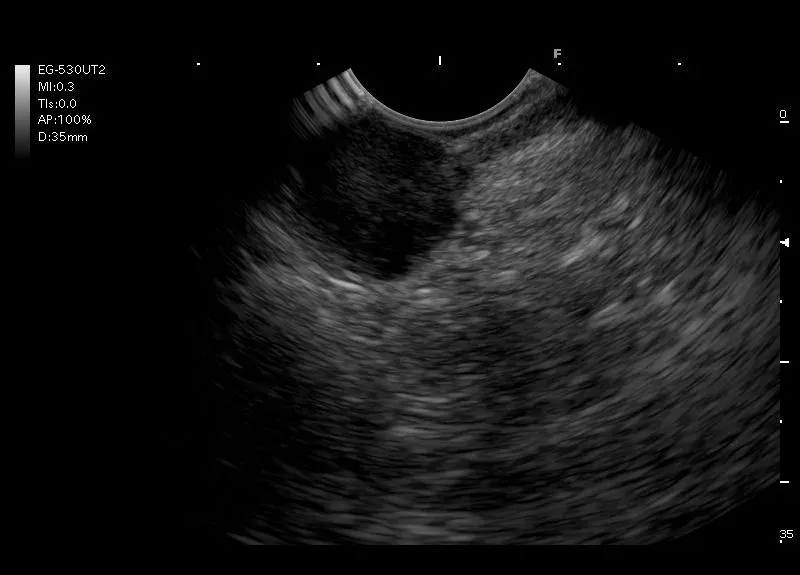

Zmiany w ścianie przewodu pokarmowego

Hipoechogeniczna zmiana w ścianie żołądka wywodząca się z warstwy mięśniowej